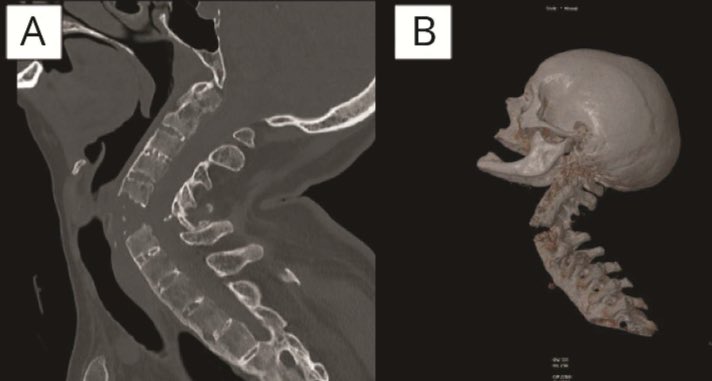

🚨 🚨 Ojo con los amantes y defensores de la quiropraxia Que no te pase a ti o a tus pacientes lo que le sucedió a esta mujer de 48 años que consultó por dolor cervical crónico, le realizaron quiropraxia y durante la sesión tuvo empeoramiento del dolor cervical y tetraplejia 👇

Que no te pase a ti o a tus pacientes lo que le sucedió a esta mujer de 48 años que consultó por dolor cervical crónico, le realizaron quiropraxia y durante la sesión tuvo empeoramiento del dolor cervical y tetraplejia